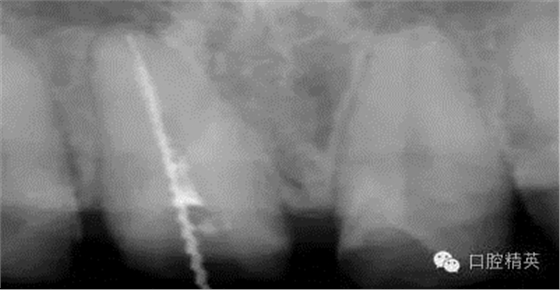

根管治療更是牙體修復(fù)的基礎(chǔ),根據(jù)術(shù)前診斷,對(duì)需要做根管治療的或有必要重新做根管治療的,一定要做到恰充,消除隱患,避免將來(lái)冠修復(fù)好后,出現(xiàn)根尖炎癥的問(wèn)題(見(jiàn)圖3、4、5)。在基礎(chǔ)工作做好后,接下來(lái)開(kāi)始牙體預(yù)備,根據(jù)跟個(gè)人習(xí)慣,選擇合適的車針(圖6、7)。